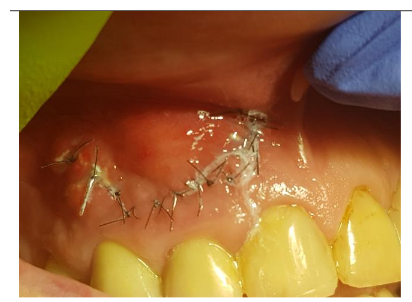

Suturation 6-0 nylon, reverse cutting needle, length 12 mm

Under local anesthesia (4% articaine with adrenaline), a trapezoidal incision was made, and extensive damage to the external lamina was observed. The cyst was carefully removed and sent for histopathology, which confirmed an inflammatory root cyst. A 3 mm apicoectomy was performed on tooth 12, and the root canal was filled with MTA. The bone defect was filled with 2 cc of Bond Apatite®, and the flap was closed without a membrane.

The patient experienced moderate discomfort in the first two days post-surgery. Sutures were removed after seven days, and follow-up radiographs showed satisfactory healing. After six months, CBCT scans revealed significant bone remodeling and regeneration of both cortical plates. No symptoms were reported during a two-year follow-up.